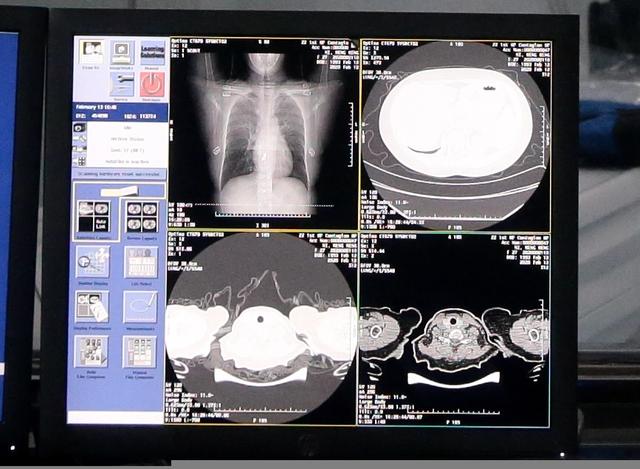

例如,达摩院AI突破了新冠肺炎样本数据不足的局限,训练了全新的AI算法模型,可在20秒内对新冠疑似患者CT影像做出判读,分析结果准确率达到96%,大幅提升临床诊断效率。技术率先在郑州小汤山投入使用。